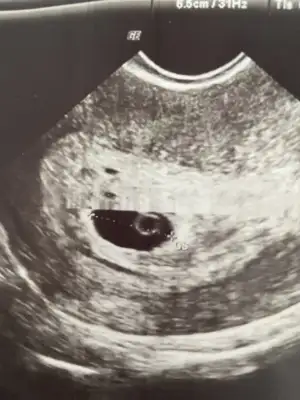

Ben de dün keseyi gördüm sizlerle paylaşıyorum canım bir sıkıntı yok haftaya kalp atışını duyarız der doktorum sağlıklı gözüküyor stres yapma bu sefer olacak dedi. İnşalalh olur 🙏

Eklentiler

• image.webp

image.webp

30,3 KB · Görüntüleme: 74

yaa maşallah sizinkisi daha büyük duruyor 🥰🥰🥰 olumlu düşün olumlu olsun canım, olumsuzlukları kafandan sil inşallah sağlıkla gelecek 🙏🙏

Doktorum olumlu konuştu alışkındım her an olumsuz olabilir hazır ol demelerine. Ama bu sefer olacak çok güzel tam hastasında dedi çok mutlu oldum. Hakkımızda hayırlısı olur inşalah 💐🙏